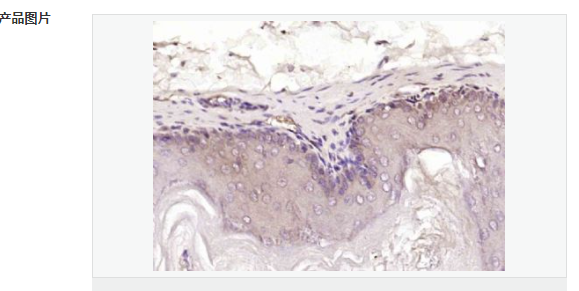

| 產(chǎn)品應(yīng)用 | WB=1:500-2000 ELISA=1:5000-10000 IHC-P=1:100-500 IHC-F=1:100-500 IF=1:50-200 (石蠟切片需做抗原修復(fù)) not yet tested in other applications. optimal dilutions/concentrations should be determined by the end user. |